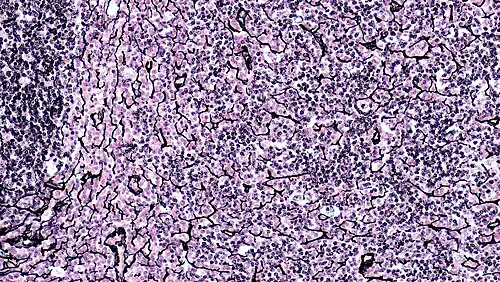

Ретикуля́рная ткань (лат. textus reticularis) — особая форма соединительной ткани[1], состоящая из так называемых ретикулярных волокон и формирующих их ретикулярных клеток. Ретикулярная ткань образует строму кроветворных органов и формирует микроокружение для клеток крови, формирующихся в них[2], однако обнаруживается и в органах, не связанных с кроветворением.

Ретикулярная ткань устроена как трёхмерная сеть, образованная стыкующимися ретикулярными фибробластоподобными[3] клетками, большинство из которых связаны с ретикулярными волокнами и окружают их своей цитоплазмой[4][2]. Благодаря отростчатой форме ретикулярные клетки выполняют механическую функцию. Они также секретируют компоненты основного вещества ретикулярной ткани — преколлаген, гликозаминогликаны, проэластин, микрофибриллярный белок[5].

Ретикулярные волокна достигают 0,5—2 мкм в диаметре и синтезируются ретикулярными клетками. Ретикулярные волокна содержат коллаген III типа и некоторых других типов, гликопротеины и протеогликаны. Они устойчивы к действию слабых кислот и щелочей, а также трипсина. Ретикулярные волокна являются аргирофильными, поскольку они выявляются при импрегнации солями серебра, которыми окрашиваются в чёрный цвет (при окрашивании гематоксилином и эозином они не видны). Аргирофильность ретикулярных волокон обусловлена с высоким содержанием углеводных цепей. К числу аргирофильных волокон также относят преколлагеновые волокна, которые представляют собой начальную форму образования коллагеновых волокон, однако ретикулярные волокна, по сравнению с преколлагеновыми, содержат серу, липиды и углеводы в высокой концентрации. В частности, ретикулярные волокна содержат 6—12 % гексоз против 1 % гексоз в коллагеновых волокнах (в отличие от ретикулярных, коллагеновые волокна содержат коллаген I типа, а не III типа). Ретикулярные волокна также красятся положительно при ШИК-реакции за счёт углеводных цепей, как и при импреграции солями серебра. Из-за малого диаметра ретикулярные волокна при окрашивании сириусом красным и визуализации с помощью поляризационной микроскопии приобретают зелёный цвет[6][7].

Ретикулярные волокна не являются уникальными только для ретикулярной ткани, но именно в ней являются доминирующими[8]. Ретикулярные волокна наиболее многочисленны в гладких мышцах, эндоневрии и строме кроветворных органов (селезёнки, лимфатических узлов, красного костного мозга), в которых они образуют ниши для развития клеток крови. Важную роль в формировании кроветворных ниш играют ретикулярные клетки, которые секретируют факторы роста, необходимые для определённых направлений развития гемопоэтических клеток[5]. Ретикулярные волокна также образуют сеть вокруг клеток некоторых паренхиматозных органов, таких как печень и эндокринные железы. За счет рыхлого расположения и малого диаметра ретикулярные волокна образуют гибкую сеть в органах, которые претерпевают изменение формы и объёма: артерии, селезёнка, печень, матка, мышцы, обеспечивающие перистальтику кишечника[9].